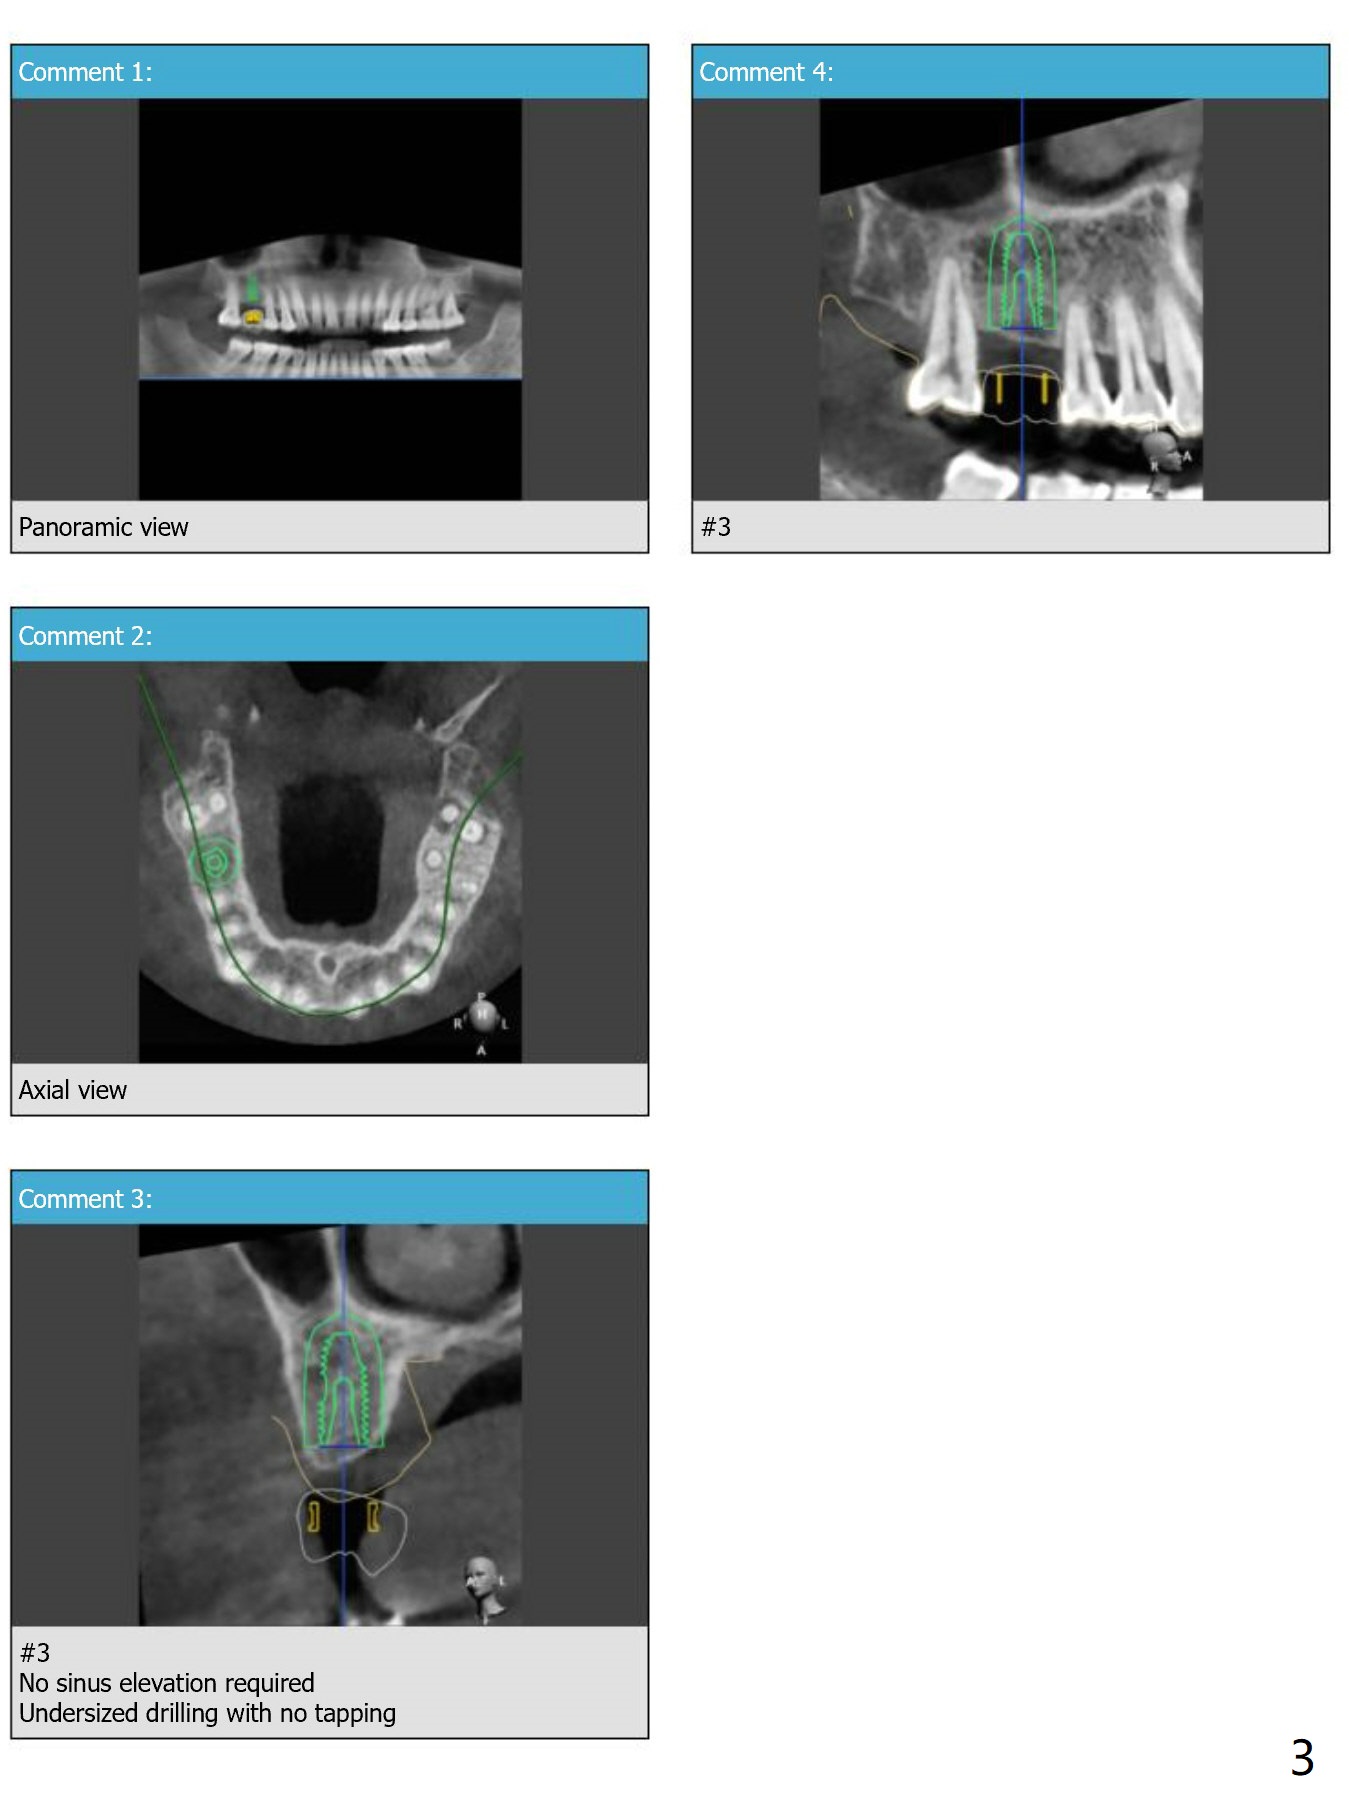

No Sinus Lift Required.  Undersized Drilling with No Tapping

Return to Upper Molar Immediate Implant, Armaments